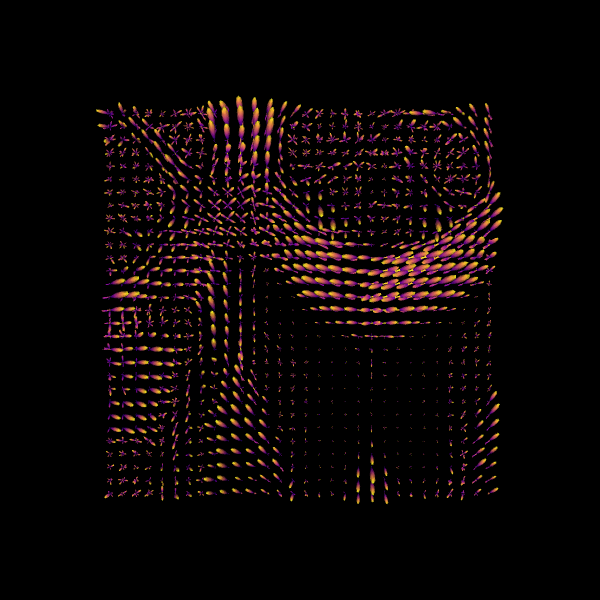

For quality assurance, we can visualize an axial slice from the direction field estimated by the CSA model. Each glyph represents a local fiber orientation derived from the ODF peaks. The underlying ODFs are not shown here.

scene = window.Scene()

scene.add(

actor.peak_slicer(

csa_peaks.peak_dirs[20:50, 55:85, 37:38], peaks_values=csa_peaks.peak_values[20:50, 55:85, 37:38], colors=None

)

window.record(scene=scene, out_path="csa_direction_field.png", size=(600, 600))

Image("csa_direction_field.png")

../_images/e401dd1b6d94fe4f2384165b5fef0c0fe2717a93e33004cc0ced94709a527f2c.png